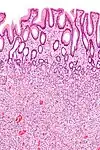

Peutz-Jeghers Polyp All digestive tract Smooth muscle bundles between nonneoplastic epithelium, "Christmas tree" appearance No